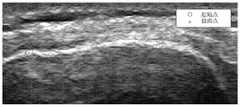

FIG. 3 is an ultrasound view of the motion tracking of bones in a joint as measured by an apparatus according to one embodiment of the present invention;

Fig. 3 shows an ultrasound image showing the tracking of the bone along twopaths 60, 65. For ultrasound, it is capable of detecting the edges of bone (bone landmarks ormarkers 70, 75). These are used to track the displacement of themarkers 70, 75 on a frame-by-frame basis to track and measure the rotation of the bone.

With respect to the graph of fig. 3, afirst line 60 indicates a change in rotation of the bone, while asecond line 65 indicates detection of amatching marker 70, 75. The detectedmarkers 70, 75 are used to calculate the difference in displacement and angle of the bone. The rotation speed is then measured by the time between image captures.